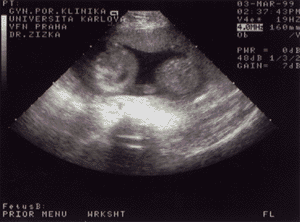

13. týden